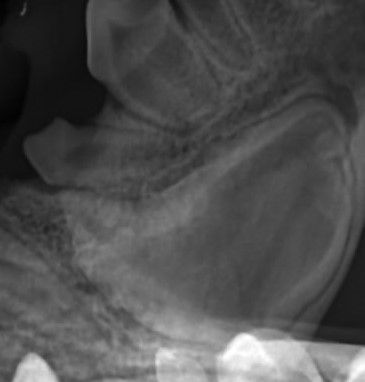

The retained canine tooth can be seen on x-ray very close to the mandibular cortex